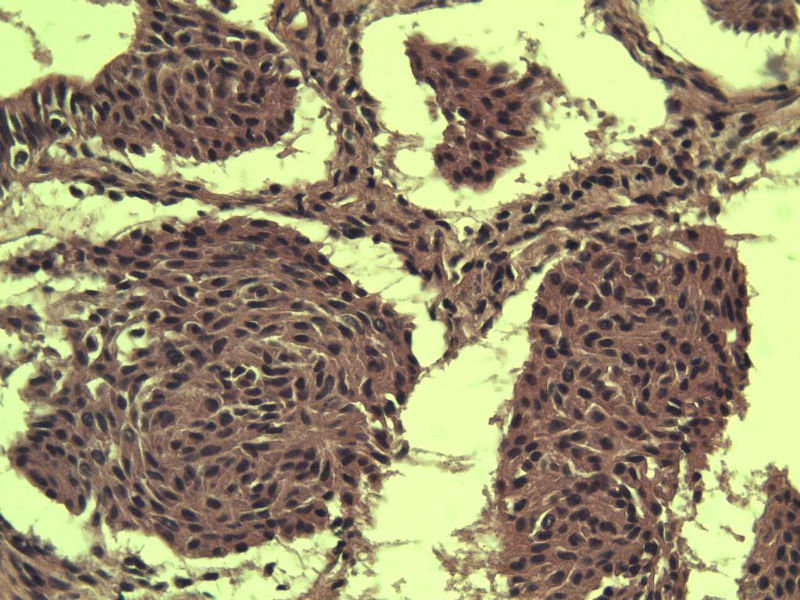

这是另外一个 40岁 经期延长 流血量增多 半年 这是蜕膜样变吧 有什么意义吗? 要报告不?